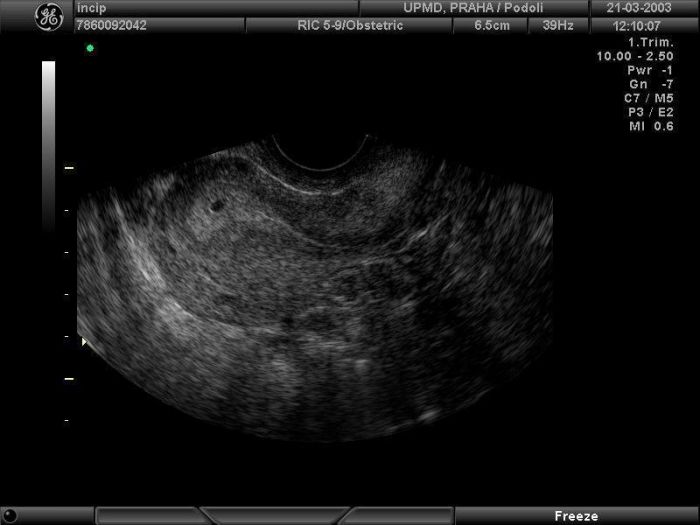

no a na UTZ byla vidět ,,jen,, vysoká děložní sliznice a těhotenská dutinka!!!!! Takže během pár dní by mělo být vidět i embryjo..... Jdu zase za týden na UTZ, taky se nedočkám..... :-)

Super Luci :) Luci, já vůbec nevím, jak si mám představit těhotenskou dutinku a jak embryo a doktorky jsem se neptala, co to je.. Prostě mi řekla, že podle UTZ jsem těhotná a v kartě mám 5-6 týden (teda v úterý to tak psala)... Vypadalo to na tom UTZ tak nějak: http://img.mimiblog.cz/f/a/4/70b207c5148f9ea98cd5e4b9007767f2_800x800.jpg nebo http://www.porodnice.cz/files/u19894/5%20tyden_vetsi_0.jpg možná spíše takto: http://www.babyonline.cz/upload/tehotenstvi-mimi/20.jpg Prostě taková "dutinka" a v ní cosi :o)))

Lulum, u mě šlo vidět jen tohle, taková tečka....a je to prý 5.tt.... za tyden jdu znova........

No vždyť píšu, že jsem v tomto mimo :o) Ale jo, asi to bylo podobné, jak to Tvoje (možná kombinace s tím mým posledním odkazem). Přišlo mi, že ten okraj dutinky byl výraznější a uvnitř byla tečka... Ale ono je to všechno i kvalitou UTZ. Bylo to taky situované na obrazovce spíše vĺevo nahoře a bylo to vzhledem k tomu snímanému prostoru poměrně malé (ale zase ne tak malé jako na Tvém fotu). Ale ono je to i tím, jak velké rozlišení třeba ten UTZ má a tak... Prostě za 2 týdny uvidím :o) Tý jo, Ty jdeš znovu už za týden? A to máš nějaké rizikové těhu nebo jen tak? :o) Nebo je setřička popř. doktor/ka známá? :o) Holky, které jste byly u Dr. také chodítě tak často? Vyzvídám a ptám se, protože checkuju tu mou doktorku :o) Ale jinak mě připadá dostačující, že jsem byla teď na začátku - a pak až cca v 7.-8. týdnu - a to už prý půjdu jakože do poradny. Tak jsem se jí ptala kam a ona, že jako k ní, ale že to už je poradna pro těhotné :o)))) Kdyby bylo po mém, tak jdu třeba až v 10. týdnu - to bych měla jistotu a věděla bych, že už by to srdíčko jo být vidět mělo.. takto chodit každý týden a pořád slyšet uvidíme - to je na palici, ne? :o) Ale chápu také pozitiva - vidět ten UTZ. :o)